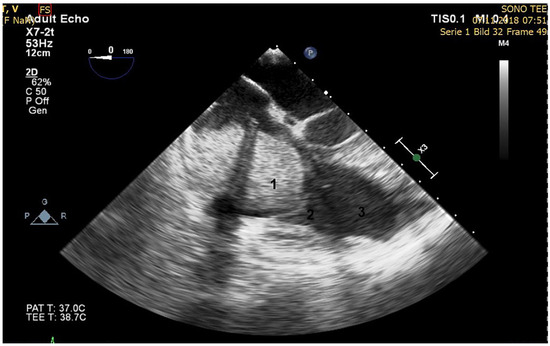

When performing revascularisation of a chronic total occlusion, contralateral injection is essential to visualise the distal bed of the occluded vessel, adding to procedural success. Here we describe a case of antegrade recanalisation of a left anter...